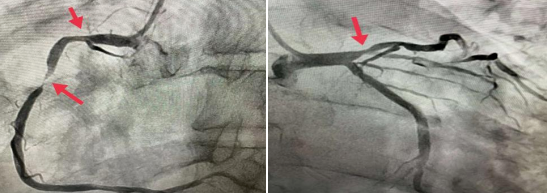

今年53岁的王大爷,冠状动脉造影结果提示右冠状动脉中段狭窄99%,右冠近端及前降支近端狭窄在70%左右,处于临界病变,要不要都植入支架呢?

马登峰对王大爷狭窄的血管进行FFR检测,将一根压力微导管送入狭窄血管的远端,通过连接的仪器进行测试,右冠近端与前降支近端测试FFR值分别为0.91和0.85,均提示不需要植入支架治疗,只需要在右冠中段狭窄99%处植入一枚支架。